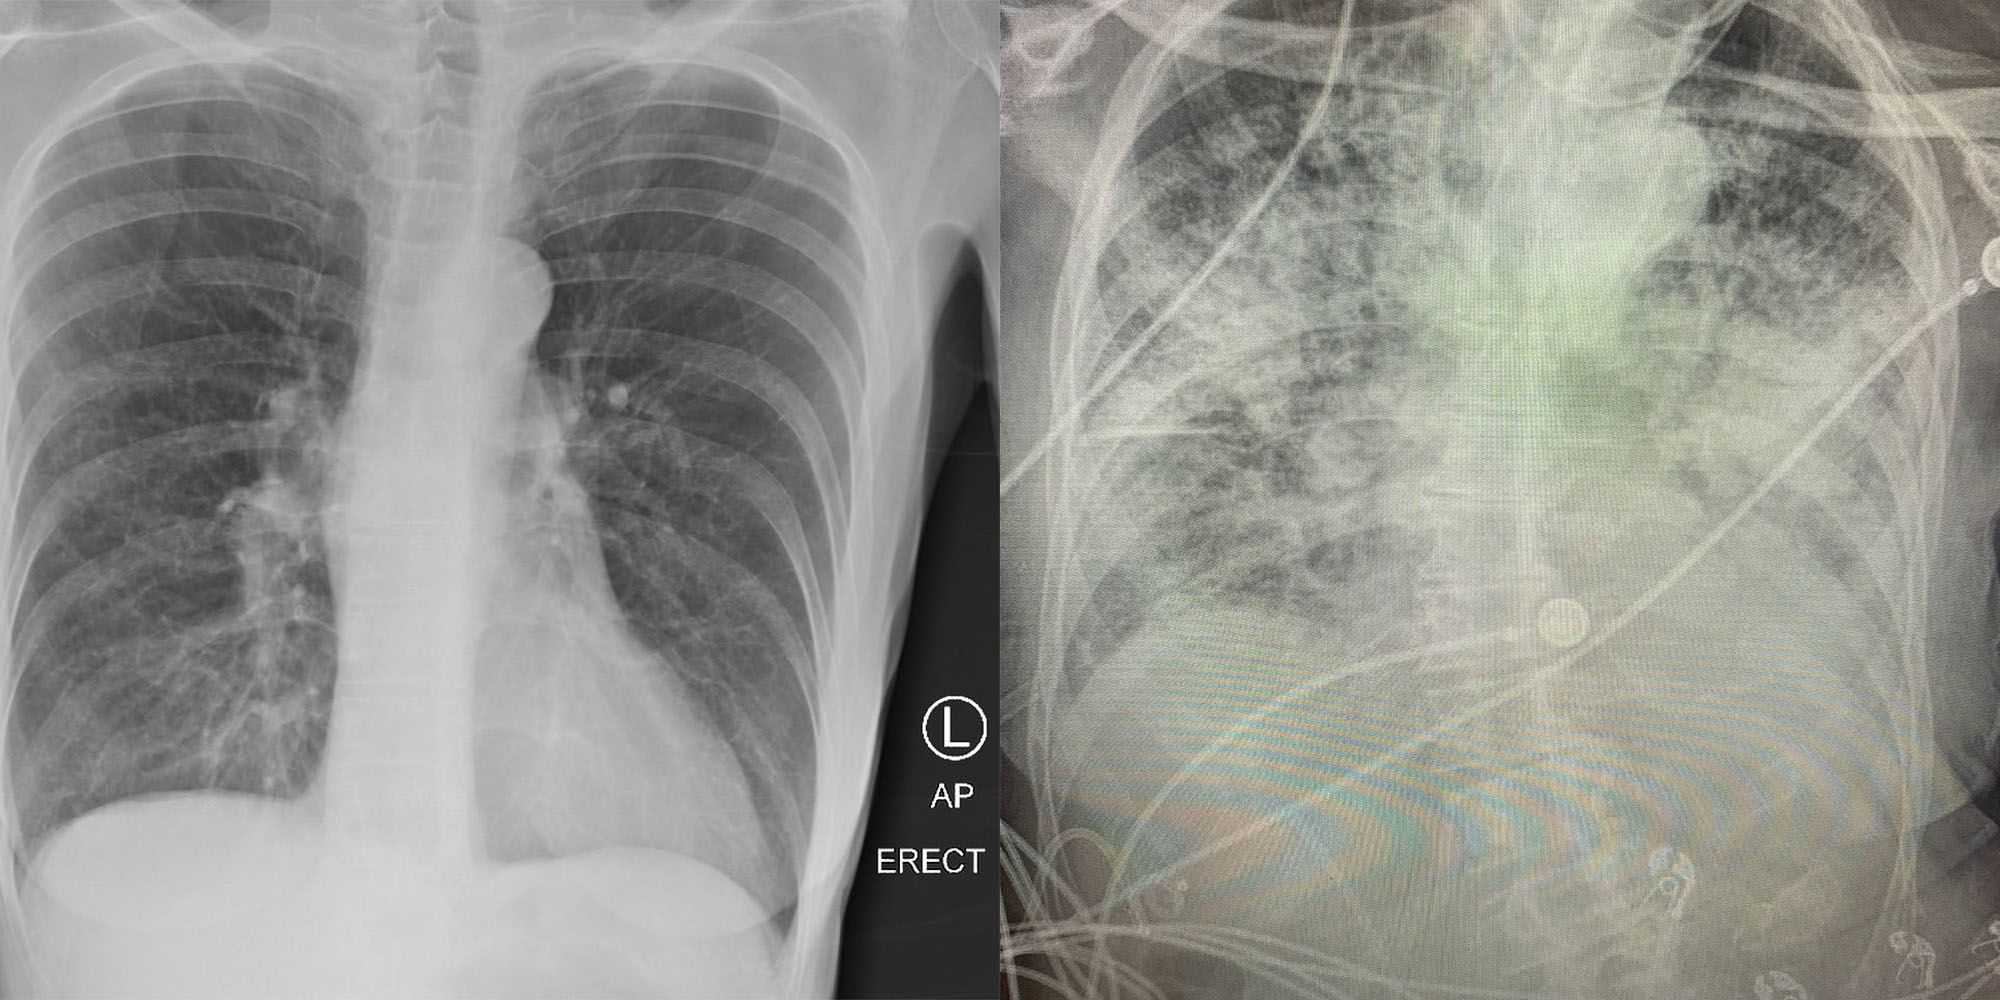

Links eine Raucher-Lunge, rechts die Lunge eines Covid-Erkrankten